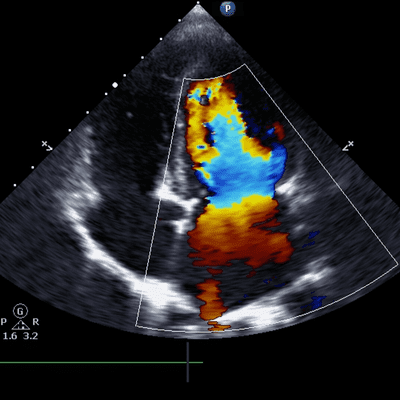

Ultrasound is also called sonography or ultrasound scanning. Images of the testicle and the surrounding tissues in your scrotum obtained in a testicular ultrasound. Testicles produce sperm and male sex hormone i.e., testosterone are the primary male reproductive organs.

• Evaluation and detection of varicoceles, which are varicose spermatic veins.